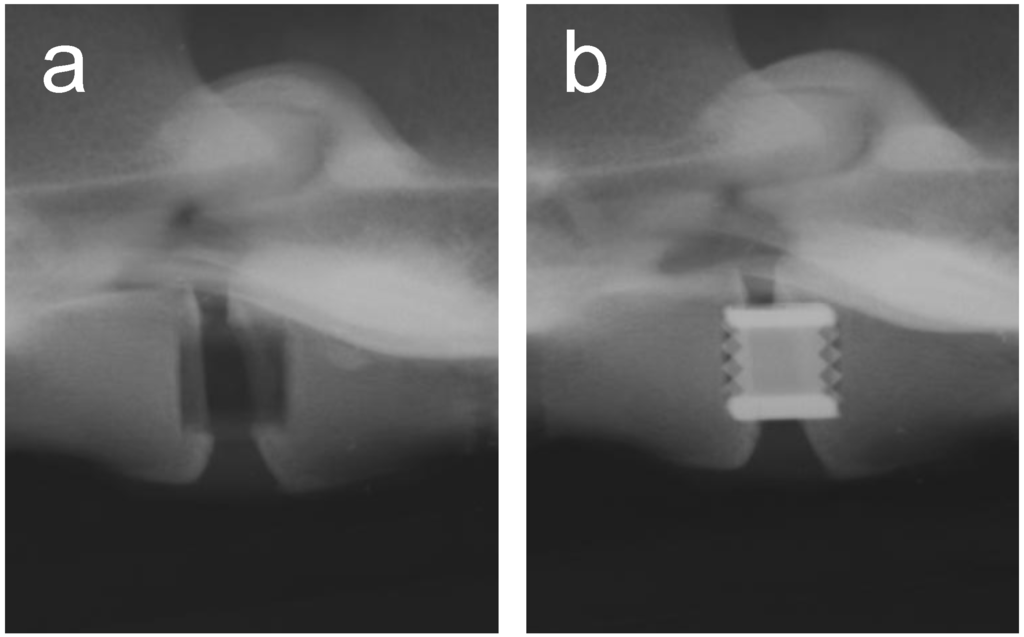

Metals and/or alloys have proven to be successful, although drawbacks do exist. In spinal surgery, amongst others, permanent materials such as metals (and non-resorbable polymers) remain susceptible to long-term complications such as migration [103], wear [61], late foreign body reaction [61,104] and infection [105]. The inflammatory reaction is, in some cases, the result of the inevitable corrosion of alloys in vivo (often referred to as particle disease), and also in the spine [106,107]. In other cases, the aforementioned micro-motion through the spinal motion segment may lead to particle debris [22]. Therefore strategies to minimize implant related problems have been devised such as removal of the implant after fulfilling its purpose in every patient [108], or to selectively remove the implant in symptomatic patients [95], which in return can cause neurovascular injury or refracture [95]. In the USA, retrieval surgeries of the spine were reported in 25-40% of the patients [109,110,111]. Furthermore, metallic spinal implants are strongly radiopaque on roentgenograms, which is the most widely used follow-up imaging after spinal surgery [112] (see Figure 3). This results in an obscured view and therefore hampered assessment of fusion, since the presence of a bony bridge throughout the spinal implant can not be seen [112,113,114,115]. Not only do metals/alloys interfere with simple x-ray films, they will therefore also interfere with computer axial tomography scanning (CAT) and cause artefacts (scattering) with magnetic resonance imaging (MRI) [100] In contrast, the presence of a bony bridge on a plain roentgenogram in radiolucent spinal implants can be visualized and does correlate with surgical exploration, considered the gold standard [116]. Radiolucent spinal implants are generally made from non-degradable polymers such as polyetheretherketone (PEEK) and will also not interfere with CAT scans or MRI scans. However, in a similar fashion as metallic cages, non-degradable cages will remain susceptible to similar long-term complications. Development of degradable spinal cages will not only result in optimal assessment of spinal fusion during follow-up using x-ray films (see Figure 4), CAT scans or MRI scans, but also avert potential long-term complications, resulting in a patient-friendly and cost-effective treatment option.

Figure 4. Lateral roentgenogram of a goat, using both a radiolucent cage and polymer cage filler (a) directly postoperative and (b) prior to sacrifice, 6 months after surgery, in which bone formation in the cage, indicated by the white arrows, can be seen.